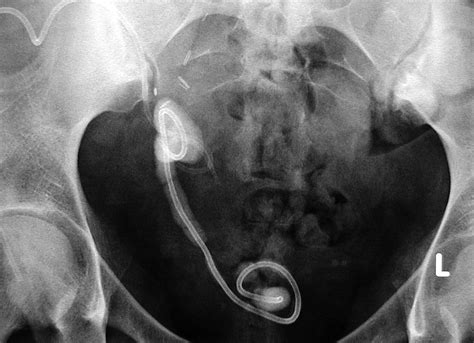

A bladder stent, commonly referred to by medical professionals as a ureteral stent, is a thin, flexible tube made of medical-grade plastic or silicone. It is placed within the ureter—the duct that carries urine from the kidney to the bladder—to ensure that urine flows freely, especially after surgery or if the ureter is narrowed due to a stone or other obstruction.

The stent acts as a temporary internal drainage system, allowing the ureter to heal without the risk of blockage. While effective, these stents are generally designed for short-term use and must be removed once the underlying condition has resolved. Leaving a stent in for too long can lead to complications such as infection, encrustation (mineral buildup), or discomfort.

• ureteral stent removal